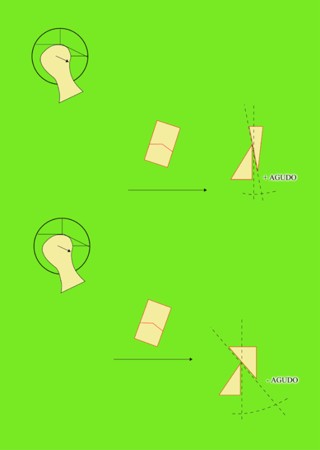

Primera Parte RESUMEN: La alta complejidad inherente a los procedimientos de Rehabilitación Oral, obligan al profesional que la ejerce a basarse en parámetros multidisciplinarios, a veces lo suficientemente intrincados que hacen imposible la práctica de la misma, sin la presencia en su mente de una clara concepción de la Oclusión. The extreme complexity of Oral Procedures, make it imperative for the working professional to rest on multidisciplinary parameters, sometimes so complex that make impossible its practice without the presence of a clear idea of Oclusion. DESARROLLO Suele ser sumamente árido el abordaje de un tema como Oclusión, desde la perspectiva de nuestro diario trabajo ,con todo el strees que este conlleva, con toda la lucha que significan citas, honorarios, diferentes personalidades de los pacientes, inquietudes de los mismos, etc. «LA MEJOR OCLUSIÓN ES LA QUE TIENE LA MEJOR DESOCLUSIÓN» Básicamente, podemos como desde hace ya muchos años se viene haciendo; clasificarlos en: A)Determinantes Posteriores (fijos) Más contemporáneamente, en: I-Mecanismos Primarios: A.T.M. GUIA ANTERIOR INCLINACIÓN DEL PLANO OCLUSAL CURVA SAGITAL DE SPEE FORMA DE LA ARCADA III-Mecanismos Elementales CRESTAS TRIANGULARES INTERNAS Analicemos cada uno de ellos: Es evidente, que la reproducción de las características de la A.T.M., en nuestro aliado fundamental, el Articulador; es imprescindible. Partiendo de la premisa de obtener una OCLUSIÓN MUTUAMENTE PROTEGIDA, para luego arribar al concepto de OCLUSIÓN MUTUAMENTE COMPARTIDA, concepto este que desarrollaremos durante el transcurso de las distintas entregas, analizaremos cada uno de los FACTORES DETERMINANTES DE LA OCLUSIÓN. El primero de ellos, por ser fijo e invariable, solo diremos que: son sus INCLINACIONES PLANARES, o sea : A-INCLINACIÓN DE LA TRAYECTORIA CONDILEA C-BENNET INMEDIATO articuladores totalmente ajustables) D-DISTANCIA INTERCONDILAR. En cuanto a la GUÍA ANTERIOR, mecanismo primario y por supuesto anterior, provee al cuerpo mandibular; del camino a recorrer durante las excursiones protrusivas y lateralidades, a través del vínculo entre las piezas dentarias anteriores, superiores e inferiores. En un corte sagital, podemos observar la relación entre estos donde vemos que se vinculan sin entrar en un contacto franco, sino más bien en una relación de vencindad muy intima a la que llamamos: PUNTO DE ACOPLAMIENTO. Otros factores fundamentales de la GUÍA ANTERIOR son : A-ALTURA FUNCIONAL B-PUNTO DE ACOPLAMIENTO En cuanto a los SURCOS, sabemos que durante una Transtrusión, las cúspides fundamentales generan surcos sobre las piezas que antagonizan. Dichos surcos proveen de una vía de escape a las cúspides antagonistas para evitar colisiones, con las indeseables fuerzas laterales cuya gravedad ya conocemos. MECANISMOS SECUNDARIOS La CURVA FRONTAL DE WILSON, se observa invertida a nivel de los caninos y de los primeros premolares. El PLANO OCLUSAL, en realidad no es ningún plano, sino la sumatoria de muchos MICROPLANOS, los cuales individualmente pueden constituir factores presentes en la OCLUSIÓN, pero auténticos problemas para la DISCLUSIÓN. La CURVA SAGITAL DE SPEE, denominada originariamente de BALKWIL-SPEE, fue concebida como una curva. El cuarto factor SECUNDARIO: el ANCHO DE LA ARCADA, es evidente que variando los ejes de rotación , alrededor de las diferentes distancias ;cambiará la dirección de los escapes (surcos), de los elementos que en el se muevan (cúspides). MECANISMOS ELEMENTALES Los CUATRO NIVELES DE OCLUSIÓN y las CRESTAS TRIANGULARES INTERNAS, constituyen de por si, la herramienta ejecutora de las funciones gnáticas. A- ELEVACIONES 1-Puntas Cuspídeas B-DEPRESIONES 1-Fosas SURCOS DE DESARROLLO De las CRESTAS TRIANGULARES INTERNAS, acentuamos su importancia en ellas dado que son las efectoras finales de la molienda, y su triangularidad debe tener su base partiendo del surco y su vértice terminando en la Punta Cuspídea, condición importante para evitar colisiones durante la transtrusión (movimiento de lateralidad ). EFECTOS DE LA VARIABILIDAD DE LOS FACTORES DETERMINANTES DE LA OCLUSÍON Cada uno de los determinantes influye aumentando o disminuyendo tanto la DESOCLUSIÓN como la ALTURA CUSPÍDEA INCLINACIÓN DE LA TRAYECTORIA SAGITAL INCLINACIÓN DEL PLANO OCLUSAL RADIO DE CURVATURA DE LA ÁNGULO DE LA TRAYECTORIA ALTURA DEL PUNTO DE LATERO SURTRUSIÓN / MOV. DE BENNET INMEDIATO CURVA FRONTAL DE WILSON SURCOS BIBLIOGRAFÍA Dibujos y esquemas tomados del libro: Oclusión Orgánica…un camino hacia la Rehabilitación Oral. 1)William Mc Horris,B.S.,D.D.S. Oclusión. Con especial énfasis sobre :El rol funcional y parafuncional de los dientes anteriores. 2)Von Spee , Craff(Anatomista alemán, describió la curva de compensación de la articulación de molares y premolares).CURVA DE SPEE 1.89 3)Stuart,D.»Some aspects of the inervation teeth.»Procedings of Royal Society of Medicine.20:1675,19274)Muhleman,H. y Savdir,S»Tooth movility-its causes and significance»Journal of Periodontology ,36:153,Marzo ,Abril,1965. 4)Muhleman,H. Y Savdir,S»Toothmovility its causes and significance» Journal of Periodontology,36:153,marzo,abril,1965. 5-Oclusión y Diagnóstico en Rehabilitación Oral. 6-Anatomia Odontológica. -A contribution to the study of the movementes of the mandible. 8-Celenza F.W, Nadeskin J.F.,Oclusión.Situación actual. 9-D´Amico 10-Dawson P.E. 11-Huffman -Regenos. 12-Hobo S.-Takayama H.A. 13-Lucia V.O 14-Mc Horris. 15-Mc Horris. 13-Posselt U. 16-Stuart C. 17-Vartan Veshnilian

Ahora bien, como; la variabilidad de cada uno de estos factores influye sobre nuestros patrones oclusales, es una cuestión a desmenuzar:

C- ÁNGULO DE LA TRAYECTORIA INCISAL

INCISAL

A menor angulación, mayor altura cuspídea , mayor desoclusión.